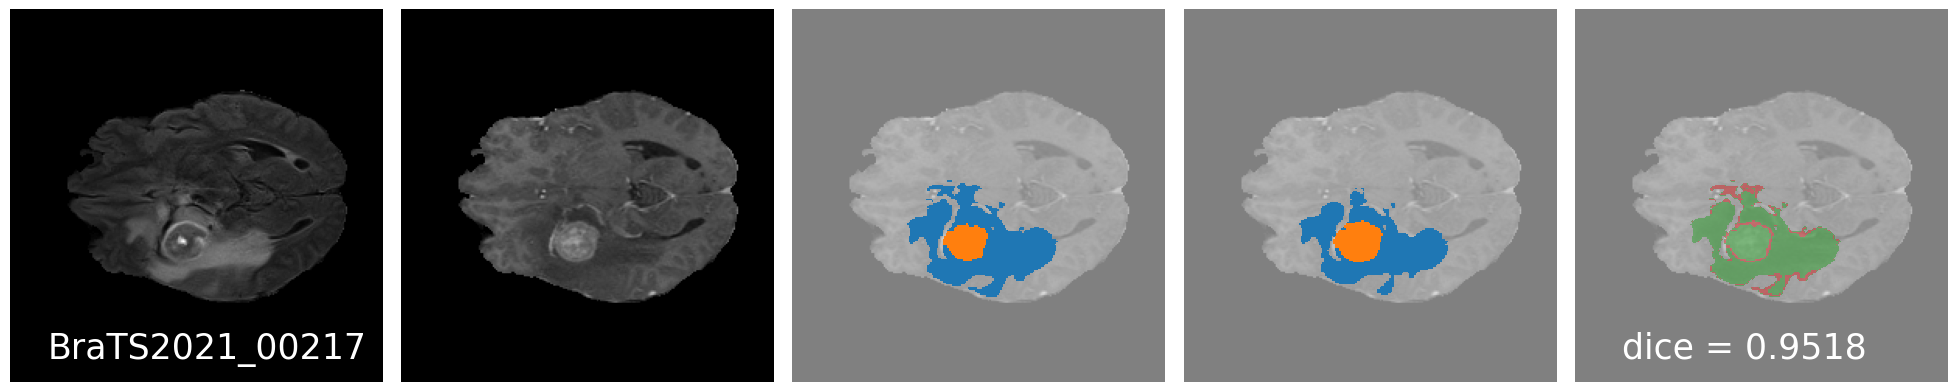

Qualitative Results : Good results

Quantitative Results